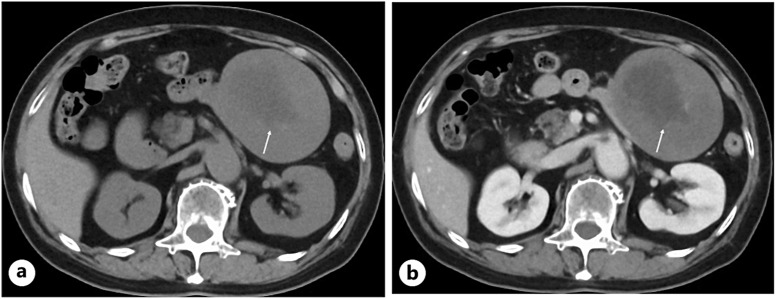

Case presentation: An 80-year-old woman was referred to our hospital due to the detection of an abdominal mass on ultrasound (US). CT showed a well-demarcated oval mass, 11 cm in size, with a central low-density area. US showed high internal echoes and enhanced posterior echoes. Magnetic resonance imaging (MRI) showed the low-density area on CT to be hypo-intense on T1-weighted images and hyper-intense on T2-weighted images. MRI further showed the central part of the tumor to be hyper-intense both on diffusion-weighted images and apparent diffusion coefficient images. Under the tentative diagnosis of a gastrointestinal stromal tumor with central necrosis, the patient underwent tumor resection, revealing the tumor to be a jejunal submucosal tumor. Pathological study showed collagen fibers with heterogeneous density and sparse proliferation of spindle cells. The center of the tumor had marked edema in addition to sparse collagen fibers. Immunostaining showed that the atypical cells were diffusely positive for β catenin and negative for S100 protein, desmin, and DOG1, leading to the diagnosis of desmoid tumor (DT).